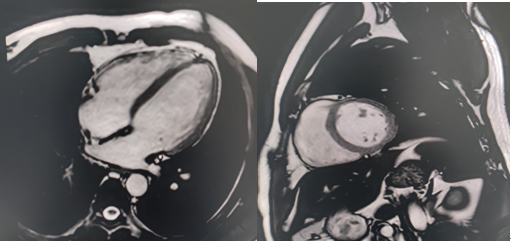

2.心血管疾病:不需要造影剂能直接观察心脏和大血管的解剖细节,可进行胸主动脉、腹主动脉、心脏电影成像、心脏增强及延迟成像等。

磁共振心脏电影成像